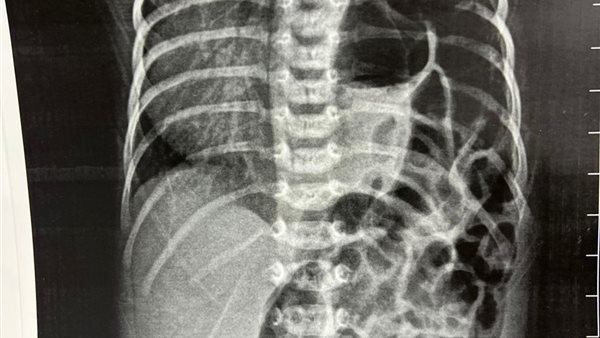

نجح الفريق الطبي بمستشفى الفيوم العام، في إجراء جراحة دقيقة ونادرة لإنقاذ حياة رضيع يبلغ من العمر 9 أيام، كان يعاني من فتق خلقي بالحجاب الحاجز (Congenital Diaphragmatic Hernia – CDH)، وذلك في إنجاز طبي يعكس مستوى الجاهزية والكفاءة داخل المستشفى.

وتُعد جراحات الفتق الخلقي بالحجاب الحاجز من أكثر الجراحات تعقيدًا في طب الأطفال، نظرًا لما تتطلبه من دقة شديدة في التشخيص والتدخل والمتابعة، وهو ما يعكس الإمكانيات الطبية المتقدمة التي يتمتع بها مستشفى الفيوم العام.